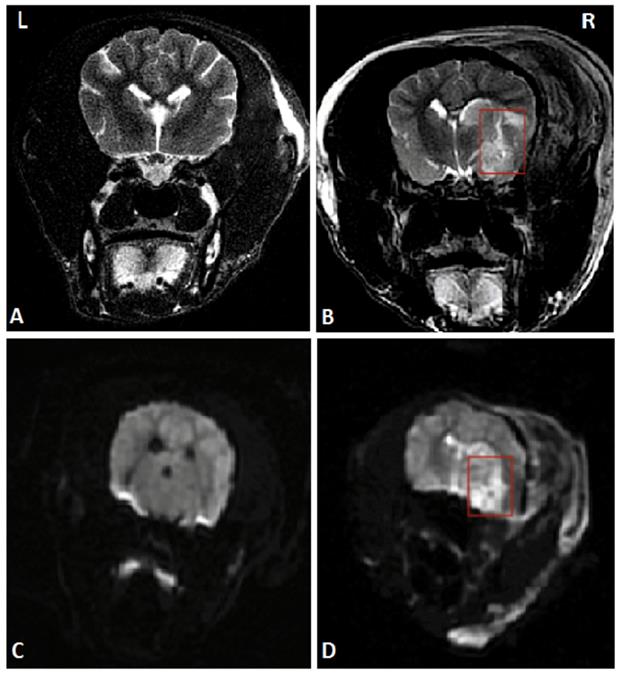

To establish the model of acute ischemic stroke, MCAO on canines was performed. After successful anesthesia, right craniotomy was performed to expose the trunk of the right middle cerebral artery under a microscope. The trunk was stanched by bipolar electrocoagulation and then cut off. Detailed operational procedures were shown in the previous study [12]. Magnetic resonance imaging (MRI) of the head was performed 24 hours after the operation to ensure the success of the stroke model. The MRI images are shown in Figure 1.

Figure 1

A head MRI that was performed 24 hours after MCAO suggested the right temporal lobe infarction, marked by red rectangles. (A) and (C) Coronal MRI scan of the sham-operated group in T2WI and DWI respectively. (B) and (D) Coronal MRI scan of the AS group in T2WI and DWI respectively. Abbreviations: AS: acute stroke; SGA: stellate ganglion ablation; MCAO: middle cerebral artery occlusion; MRI: magnetic resonance imaging; T2WI: T2 weighted imaging; DWI: diffusion weighted imaging.